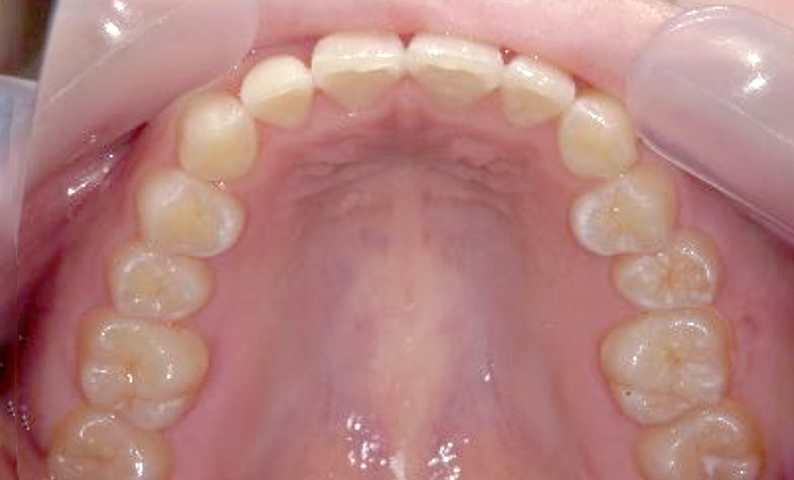

症例:上下顎の部分矯正

症例_002 前歯「捻転歯」症例

治療期間:10ヶ月金額:54万円+税30代女性少しのねじれ捻転歯前歯の突出感